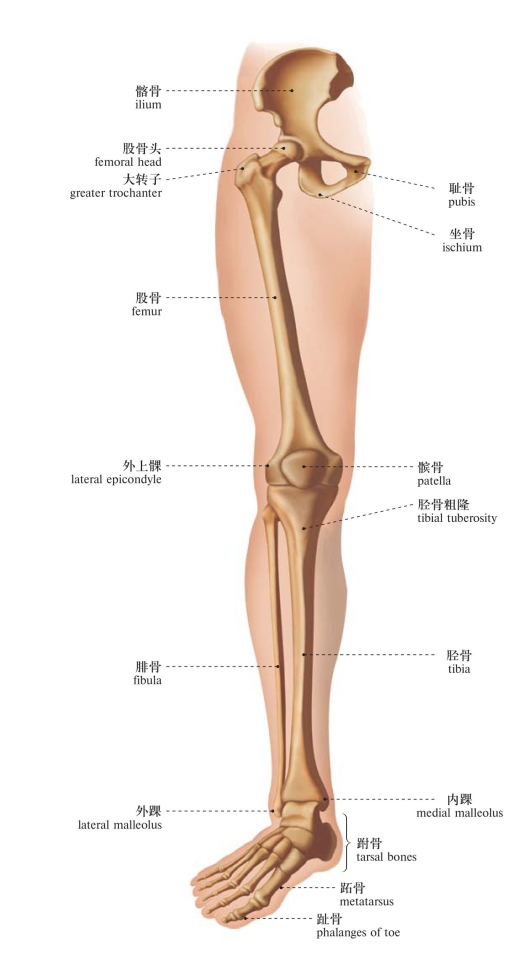

图100 下肢骨(前面观)

Bones of the lower limb (anterior aspect)